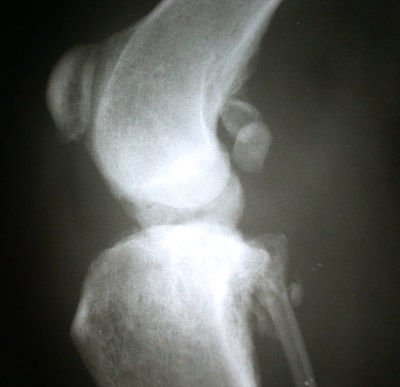

Eitrige Enzündung des Kniegelenkes